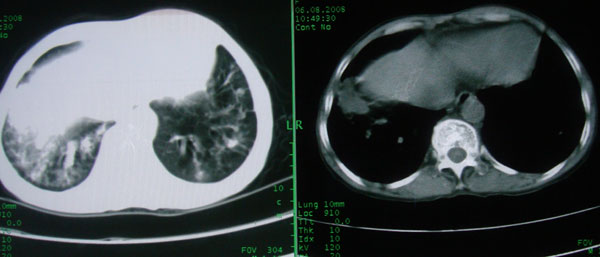

标题: CT15046:F59Y,咳嗽间断咳血丝痰就诊. [打印本页]

咳嗽\间断咳血丝痰就诊.

考虑支气管扩张并感染

1慢支伴感染;右下肺周围型肺癌。

本例应该是“慢性疾病并发多种合并症”即:慢支并感染并支气管扩张征!结合病灶分布 形态分析,不除外合并“继发性肺结核”!

慢性支气管炎伴全小型肺气肿、支气管扩张、感染、间质纤维化。

多考虑支气管扩张并感染,双下肺继发性肺结核不除外

周围型肺癌征象不明显,应不予首先考虑

考虑支气管肺泡癌可能性大

慢性支气管炎伴全小叶型肺气肿、支气管扩张、感染、间质纤维化